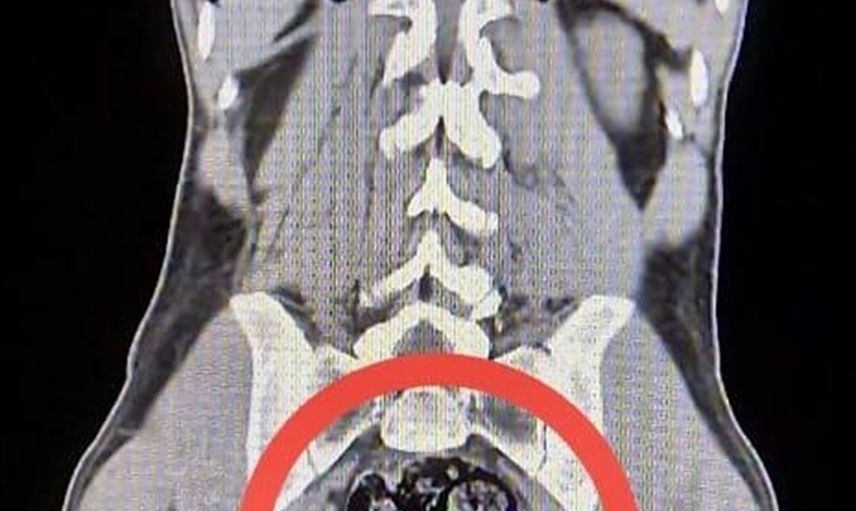

Yapılan operasyonda, Susuz ilçesinde yolcu otobüsünde gözaltına alınan zanlıların üstlerinde uyuşturucu madde bulunamadı. Ancak, sağlık kontrolü için Harakani Devlet Hastanesine sevk edilen Amır Rafıeı S.'nin mide ve bağırsaklarında 203,02 gram sentetik uyuşturucu madde tespit edildi. Bu madde, cerrahi müdahale ile çıkarıldı.